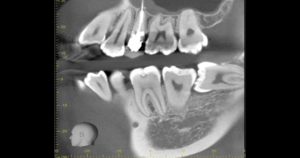

CT

CTで親知らずと神経(下歯槽管)の位置を確認しました。

親知らずと神経は一定の距離があり、麻痺などのリスクがほとんどないと判断できます。